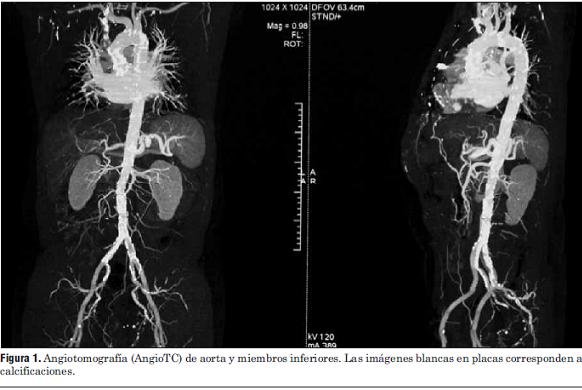

Deslizamos un balón de 18 mm de diámetro que se insufla a nivel del plano valvular aórtico (figura 3).

Figura 3.

Durante la insuflación se estimula a 180 cpm para estabilizar el balón.

Luego de la valvuloplastia y en el menor tiempo posible se procedió al avance y posicionamiento de la válvula percutánea, con posterior liberación de la misma (figura 5 a, b, c y d).